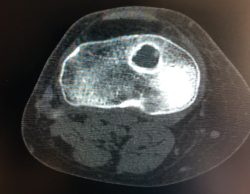

Un diagnóstico y una planificación correctos son fundamentales. En caso de rotura de plastia del LCA (Figura 3), se hace obligatoria, además de una detallada exploración, un correcto estudio radiológico completo que incluya radiología convencional y resonancia magnética (RM) –estudio de lesiones acompañantes o degeneración previa–. En ocasiones en donde la anamnesis/exploración lo justifique, pueden ser también necesarias telemetrías de extremidades inferiores, radiología forzadas (si existiera inestabilidad mediolateral) o tomografía axial computarizada (TAC) –valoración de la posición y la calidad de los túneles–.